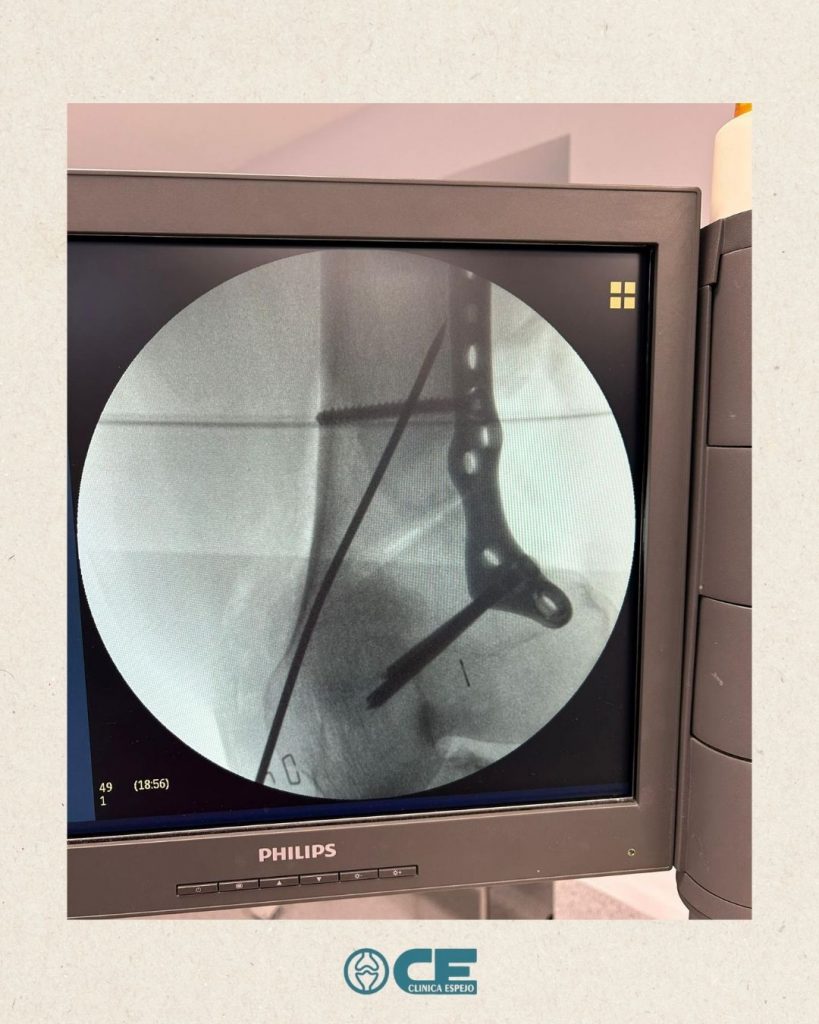

- 🏥El pasado martes nos visitó el Dr. Rusiecki desde el Hospital Universitario Dr. Negrín (Las Palmas de Gran Canaria) de la mano de @newclip_iberia para asisitir a una sesión quirúrgica de osteotomías complejas en @vithas_hospitales

¡Esperamos que disfrutaras la jornada dura de trabajo!🙌🏼Editado